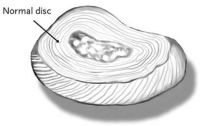

An intervertebral disc is a strong ligament that connects one vertebral bone to the next. The discs are the shock-absorbing cushions between each vertebra of the spine. Each disc has a strong outer ring of fibers, called the annulus fibrosus, and a soft, jelly-like center, called the nucleus pulposus. The annulus is the strongest area of the disc and the ligament that connects each vertebra together. The nucleus, or center of the disc, is hydrated and serves as the main shock absorber. Discs in the spine increase in size from the neck to the low back as there are increasing needs for shock absorption due to weight and gravity. These specific disc ligaments function just like knee ligaments and shoulder ligaments do. They allow the spine to move so we can bend forward, backward and sideways. Just like other ligaments, the discs can be injured.

The annulus can tear or rupture anywhere around the disc. If it tears and no disc material is ruptured, this is called an annular tear and can be extremely painful as the outer fibers carry pain signals. This tear will heal with scar tissue over time but is more prone to future tears and injury. If the annulus tears and the center nucleus can squeeze out, a piece of the disc from the center or outside portion can break off and extend outward. A disc herniation, by definition, is displacement of disc material beyond the normal confines of the disc space. The terms disc protrusion, disc bulge, disc herniation, ruptured disc, and slipped disc all mean the same thing and imply that disc material has left the normal disc space.

An intervertebral disc is a strong ligament that connects one vertebral bone to the next. The discs are the shock-absorbing cushions between each vertebra of the spine. Each disc has a strong outer ring of fibers, called the annulus fibrosus, and a soft, jelly-like center, called the nucleus pulposus. The annulus is the strongest area of the disc and the ligament that connects each vertebra together. The nucleus, or center of the disc, is hydrated and serves as the main shock absorber. Discs in the spine increase in size from the neck to the low back as there are increasing needs for shock absorption due to weight and gravity. These specific disc ligaments function just like knee ligaments and shoulder ligaments do. They allow the spine to move so we can bend forward, backward and sideways. Just like other ligaments, the discs can be injured.

The annulus can tear or rupture anywhere around the disc. If it tears and no disc material is ruptured, this is called an annular tear and can be extremely painful as the outer fibers carry pain signals. This tear will heal with scar tissue over time but is more prone to future tears and injury. If the annulus tears and the center nucleus can squeeze out, a piece of the disc from the center or outside portion can break off and extend outward. A disc herniation, by definition, is displacement of disc material beyond the normal confines of the disc space. The terms disc protrusion, disc bulge, disc herniation, ruptured disc, and slipped disc all mean the same thing and imply that disc material has left the normal disc space.